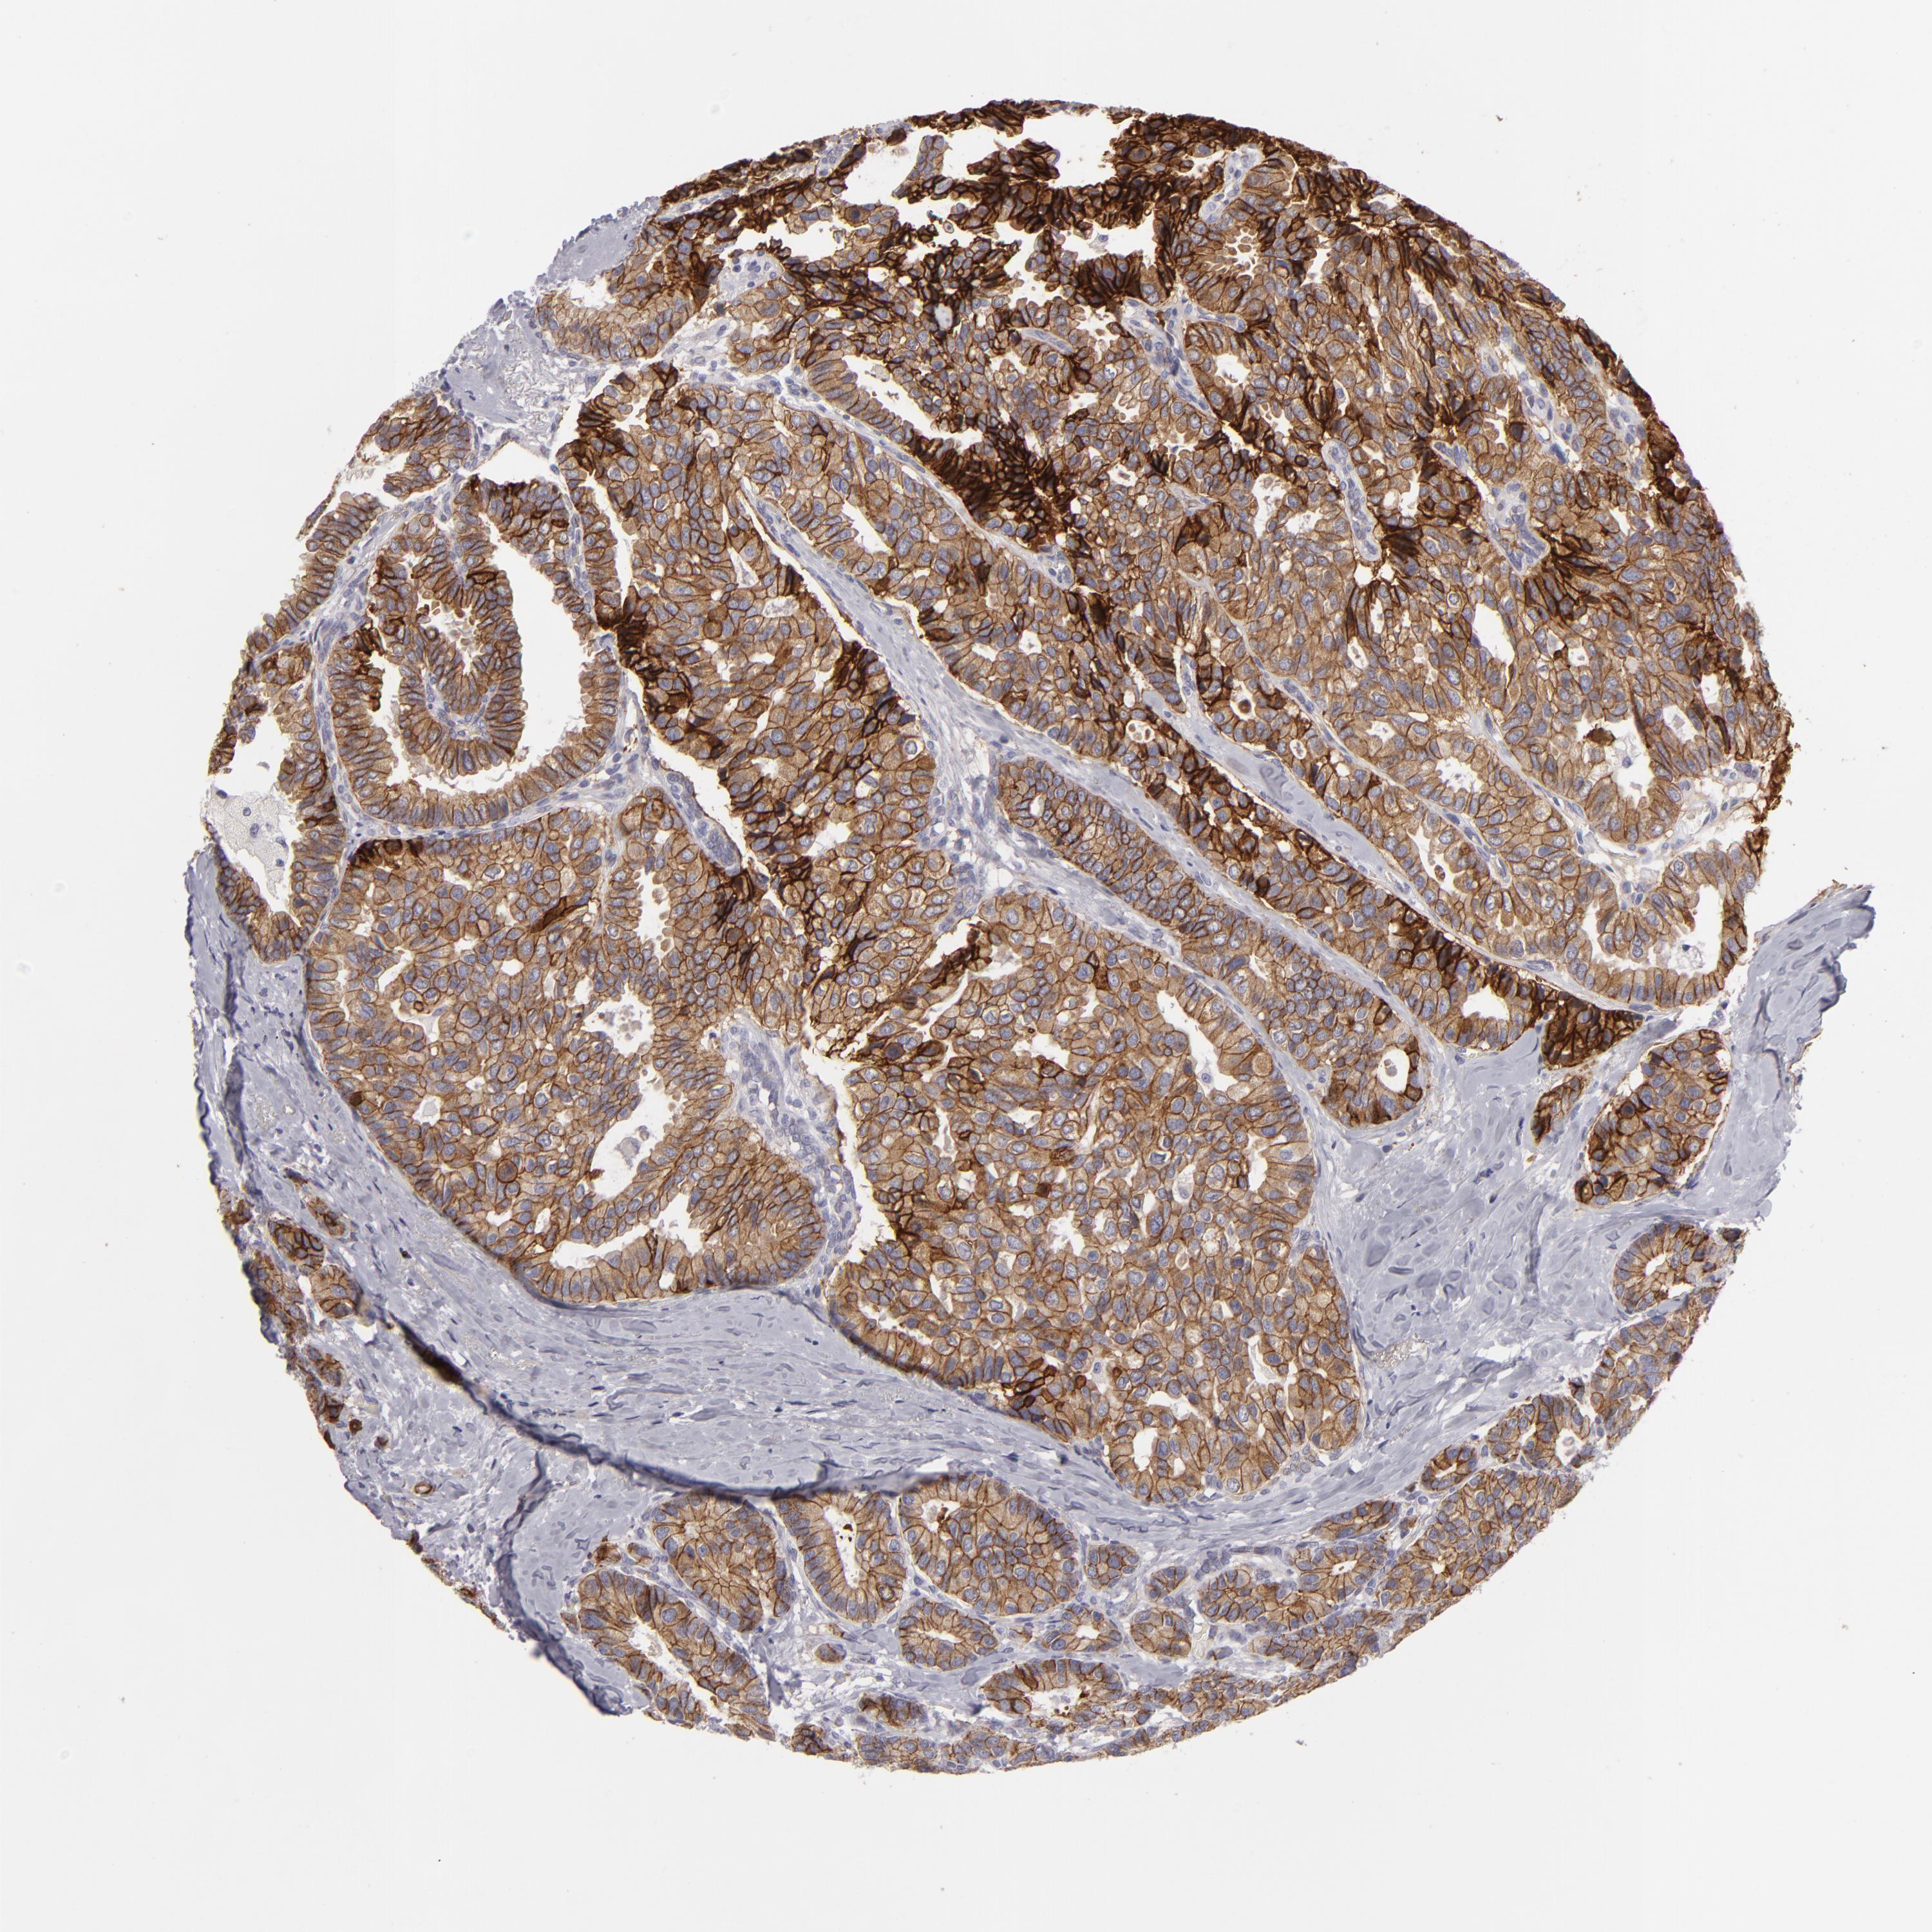

CANCER BREAST CANCER Show tissue menu

BRCA TCGA BRCA VALIDATION PROTEIN EXPRESSION